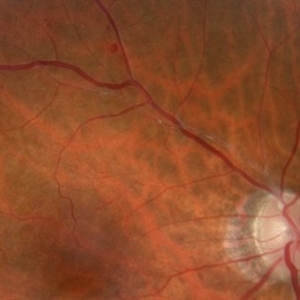

BRAO (3 files)

BRAO (3 files)

BRAO (3 files)

BRAO (3 files)